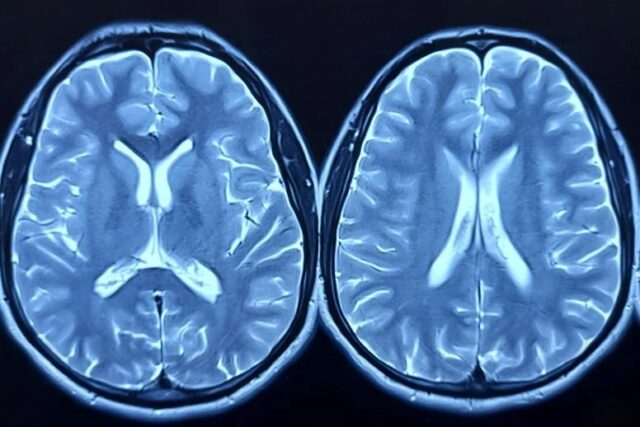

En lo que se considera el estudio más grande de su tipo utilizando tejido cerebral de donantes afroamericanos, científicos de la Universidad de Boston identificaron numerosos genes cuyos niveles de actividad diferían entre casos de Alzheimer y controles. Muchos de estos genes no habían sido vinculados previamente con la enfermedad mediante otras investigaciones genéticas. El resultado más sorprendente fue un aumento significativo en la expresión del gen llamado ADAMTS2 en el tejido cerebral de personas con la enfermedad confirmada por autopsia.

Para realizar este análisis, el equipo recolectó muestras de la corteza prefrontal post-mortem de doscientos siete donantes afroamericanos a través de diversos centros de investigación financiados por el gobierno. El gen ADAMTS2 emergió como el más alterado y también ocupó el primer lugar en un estudio separado que analizó tejido cerebral de una cohorte mucho más grande de ascendencia europea. En dicho trabajo previo, se comparó la expresión genética entre personas con síntomas cognitivos y aquellas que permanecieron resilientes a pesar de tener patología cerebral.